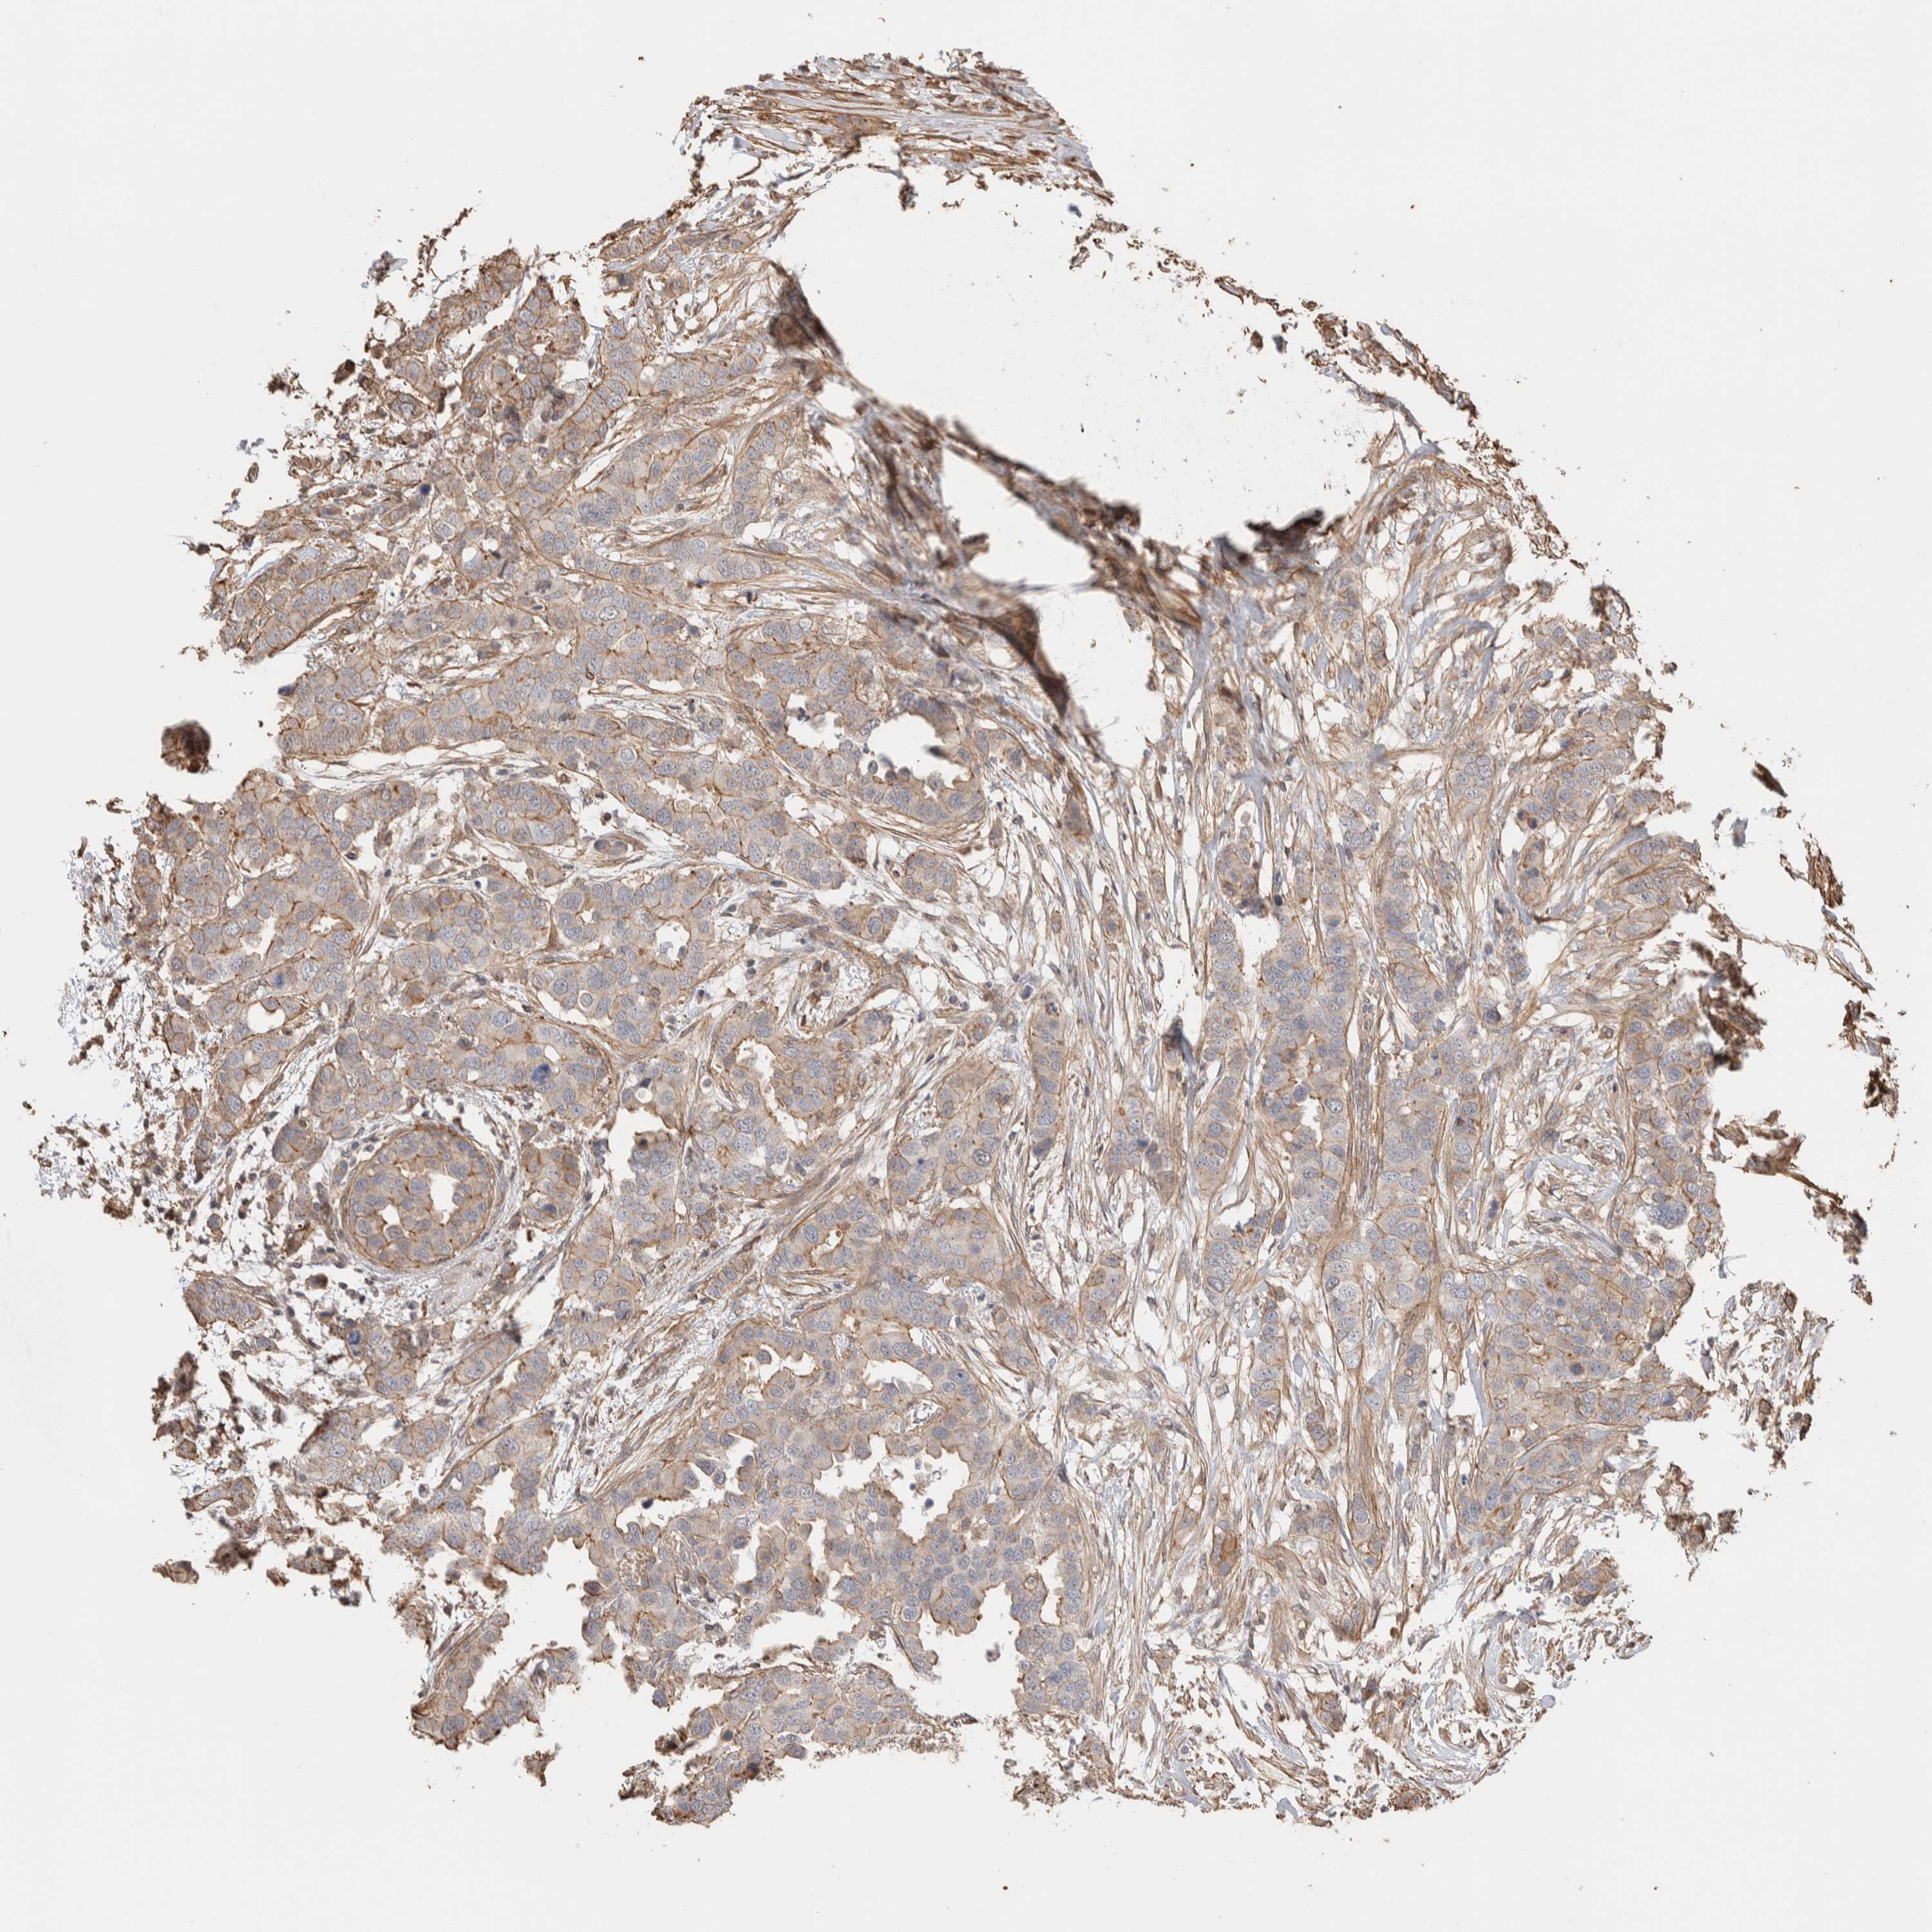

CANCER BREAST CANCER Show tissue menu

BRCA TCGA BRCA VALIDATION PROTEIN EXPRESSION